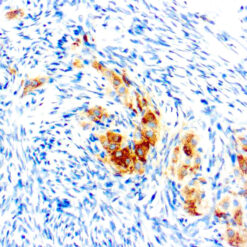

Calponin-1

Multiple isoelectric variants of calponin have been identified but only two molecular weight isoforms exist (34kDa and 29kDa). Expression of the 29kDa form, I-calponin, is primarily restricted to muscle of the urogenital tract, whereas the higher molecular weight variant has been demonstrated in vascular and visceral smooth muscle. Calponin is a calmodulin, F-actin and tropomyosin binding protein, which is thought to be involved in the regulation of smooth muscle contraction. Calponin expression is restricted to smooth muscle cells and has been shown to be a marker of the differentiated (contractile) phenotype of developing smooth muscle.

| Positive Control Tissue | Uterus |